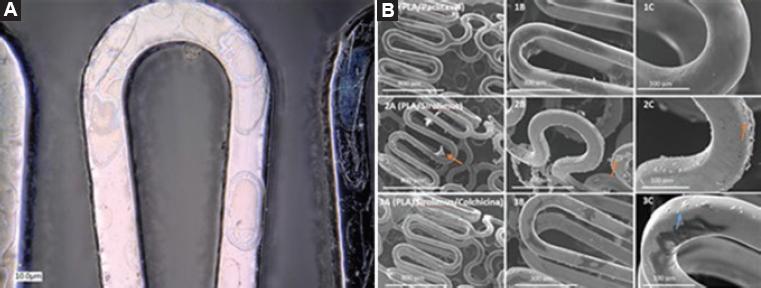

Integrity of the stents poly-lactic acid film was verified by photomicrography.

The DES were subjected to transmission electron microscopy. The polymeric coating with paclitaxel and sirolimus had a thickness of 0.600 and 0.130 μm, respectively (Fig. 2).

Figure 2 A) Electron microscopy of the polymer coating on the surface of the cobalt-chromium stent. B) Scanning electron microscopy at three magnifications (75, 200 and 500 x): 1A, 1B and 1C, paclitaxel-releasing polymer; 2A, 2B and 2C, sirolimus-releasing polymer.